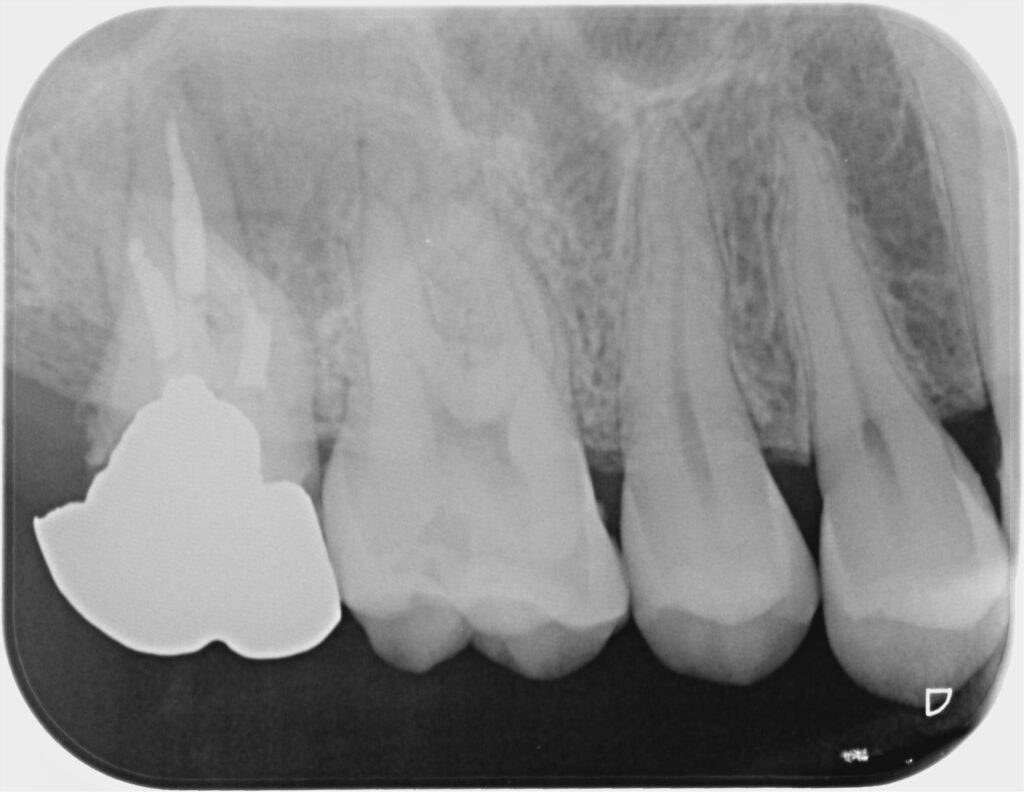

■ 術前の状態

レントゲン・CTでは、

根尖部に上顎洞に達する大きな透過像(病変)を認めました。

現在は痛みがない状態でしたが、

これは「治癒」ではなく、

👉 感染が慢性化し、症状が出にくくなっている状態

と考えられます。

また本症例では、

- 根管の湾曲が約30度と強い

- 遠心に縁下カリエスを認める

- 根尖部に吸収像(構造の破壊)を認める

という状態でした。

特に根尖部に関しては、

本来の解剖学的形態が失われている状態であり、

根管内からのアプローチのみでの改善は難しいと判断されました。